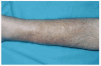

En la exploración cutánea se observaban varias lesiones. La de mayor tamaño era una placa que ocupaba los dos tercios inferiores del miembro inferior derecho, de 25 cm de diámetro mayor, bien delimitada, de color marrón, con descamación blanquecina superficial, empastada y dolorosa al tacto (fig. 1). Las otras dos lesiones estaban localizadas en cara externa de pierna izquierda y en cara anterior de brazo izquierdo, y consistían en placas de menor tamaño (3,5 y 2 cm, respectivamente), pero de características semejantes a la del miembro inferior derecho. En ninguna de las tres lesiones se observaban signos inflamatorios. No se palpaban adenopatías inguinales ni axilares.

Fig. 1.--Localizada en miembro inferior derecho, placa empastada, de color madera, con descamación superficial, sin aumento de la temperatura local.